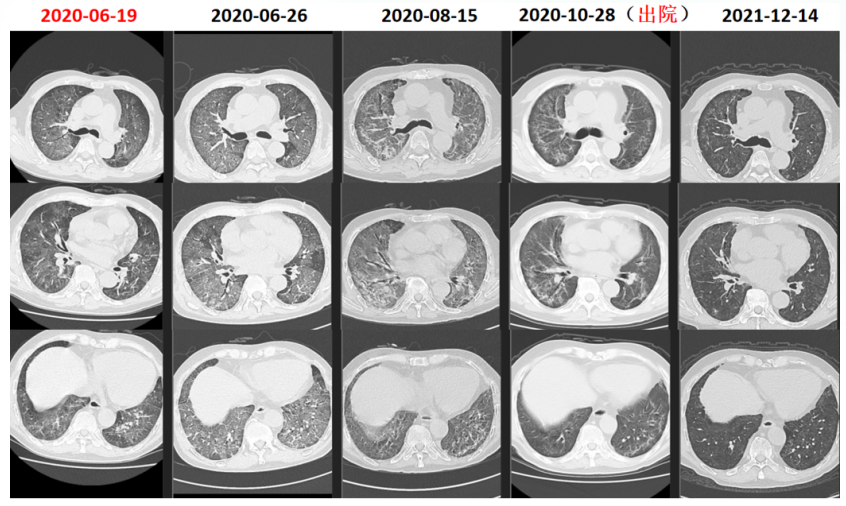

入院当天送KL-6快速进行性升高(图4)患者肺部后续出现机化和纤维化(图5)尽管整个治疗过程非常艰辛但最终预后比较满意。随访胸部CT可见病变吸收良好。

图片

5  患者住院期间胸部CT变化情况